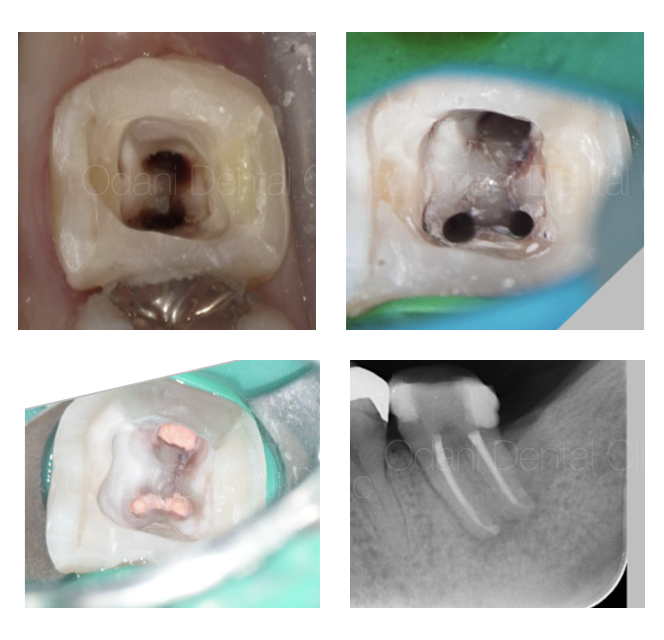

まず、虫歯部分を徹底的に除去した後、細菌が再侵入しないよう隔壁を作製しました。

そしてラバーダム防湿を行った上で、30倍まで拡大できる歯科用顕微鏡下で、根管内の清掃・洗浄を丁寧に行いました。

洗浄には、薬剤や超音波洗浄に加え、超弾性ニッケルチタンファイルやEr:YAGレーザーも併用し、根管内の細菌除去を徹底しました。

術後半年の経過観察を行ったところ、幸い治療が奏功し周囲の影が完全に消失したため、歯を保存できると判断し、かぶせものを作製して治療を終了しました。